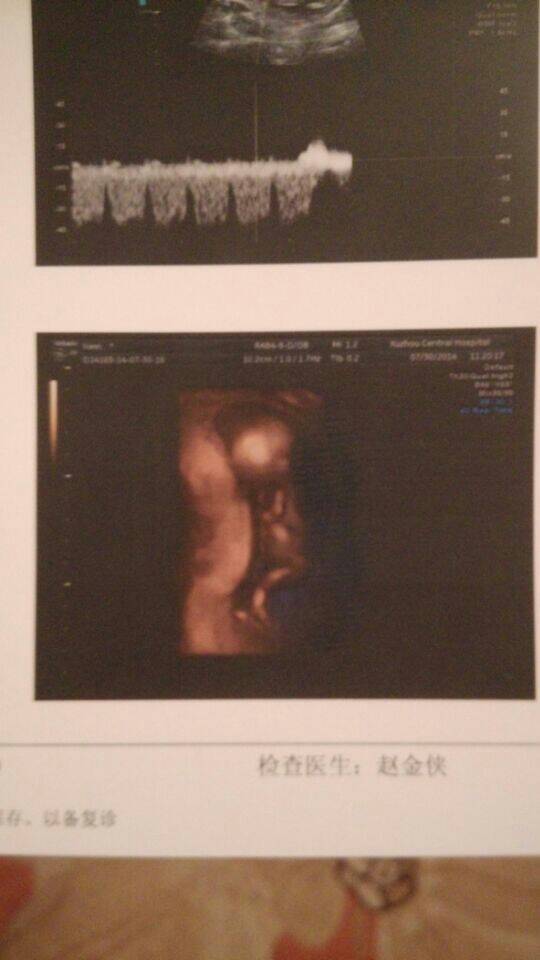

真心好奇肚子里的宝宝是男孩还是女孩啊!有没有大神可以看的出来的啊?